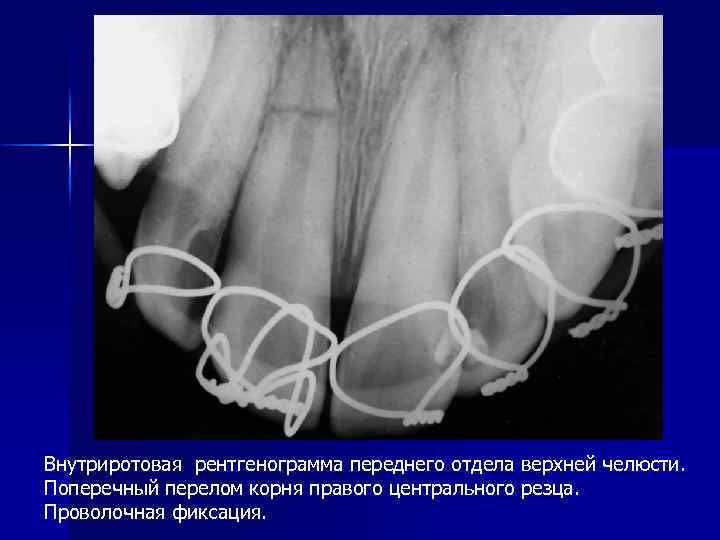

Внутриротовая рентгенограмма переднего отдела верхней челюсти. Поперечный перелом корня правого центрального резца. Проволочная фиксация.